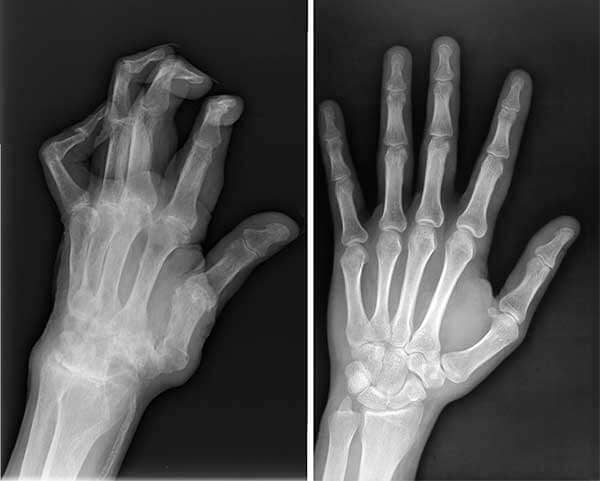

Rendgenske snimke muževljevih ruku – prije i poslije korištenja Nautubone Gela.

Muževe ruke prije i nakon tretmana Nautubone Gelom.